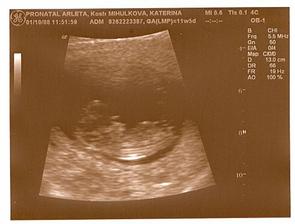

9.9.08 utz dopadl výborně, odpovídáme 8tt+1, dokonce jsem konečně viděla blikat srdíčko

1.10.08 - NT screening Kostelec nad Orlicí 10.00hodin - dopadl dobře, miminko dělalo kotrmelce a zvedalo ručičku,výsledky krve dopadly skvěle, čekáme zdravý miminko, riziko DS 1:18000